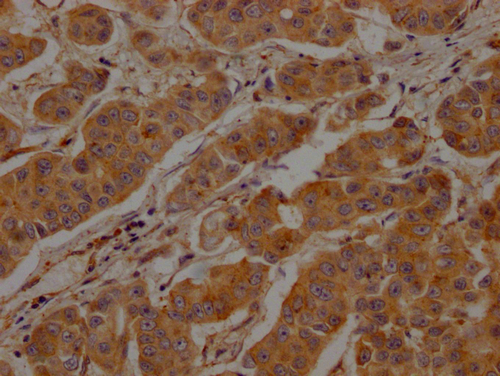

IHC image of CSB-PA005593LA01HU diluted at 1:200 and staining in paraffin-embedded human breast cancer performed on a Leica BondTM system. After dewaxing and hydration, antigen retrieval was mediated by high pressure in a citrate buffer (pH 6.0). Section was blocked with 10% normal goat serum 30min at RT. Then primary antibody (1% BSA) was incubated at 4°C overnight. The primary is detected by a Goat anti-rabbit polymer IgG labeled by HRP and visualized using 0.05% DAB.